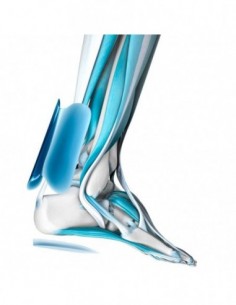

Tobilleras ortopédicas

Tobilleras ortopédicas

MalleoTrain

Tobilleras ortopédicas

Bota de Marcha Corta

Tobilleras ortopédicas